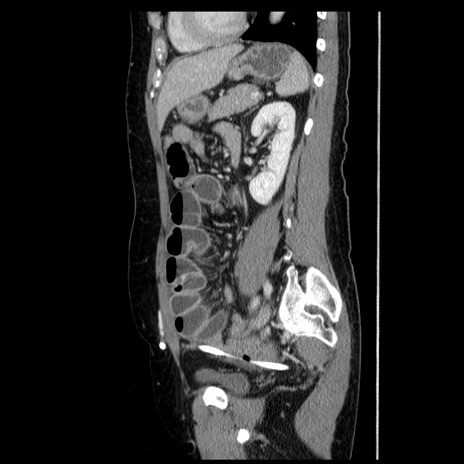

症例6(矢状断像)

【症例】50歳代女性

【主訴】下腹部痛

【現病歴】本日朝より下痢2回あり。 昼食を食べた後、嘔吐3回、下腹部痛認め、症状軽快せず、当院救急搬送。

最終食事:本日昼(生ものなし)。 昨日の夜、刺身を食ぺたとのこと。周囲に同様の症状の者なし。普段、排便は毎日あるとのこと。

【既往歴】卵巣癌術後(8年前に当院で卵巣摘出)

【身体所見】 意識清明、腹部:平坦、腸蠕動音→、やや硬、下腹部自発痛・圧痛あり、反跳痛あり、筋性防御なし。

【データ】WBC 16000、CRP 0.01